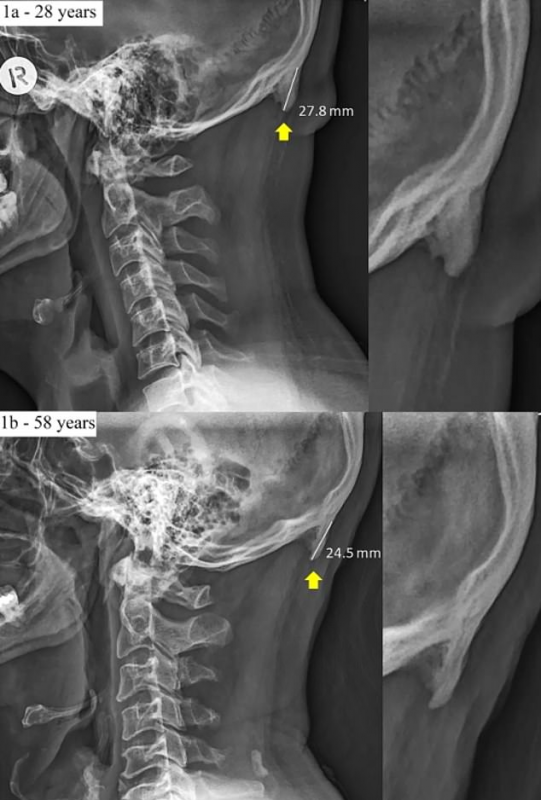

Проанализировав 1 200 рентгеновских снимков взрослых австралийцев, исследователи пришли к выводу, что у 41 процента из них в возрасте от 18 до 30 лет наблюдались такие отростки. У представителей других возрастных категорий они тоже наблюдались, однако на восемь процентов реже. В некоторых случаях наросты достигали в длину всего лишь одного сантиметра и были едва заметны, в то время как некоторые отростки были трехсантиметровыми.

Дэвид Шахар из Университета в Квинсленде рассказывает, что за второе десятилетие XXI века он сталкивался с подобными случаями все чаще. Он отметил, что подобные "дополнительные" кости называются энтезофитами и появляются, когда тело долго находится в напряжении и необычной позе.